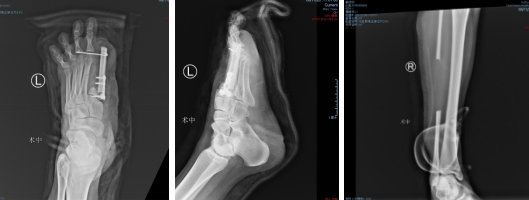

术后即刻

术后DR

术后,就是精心的后续治疗和护理了,让移植的皮瓣与创面慢慢生长“合而为一体”。一周后,观察皮瓣静脉回流正常,顺利成活。两周后,患者皮瓣感觉功能良好。